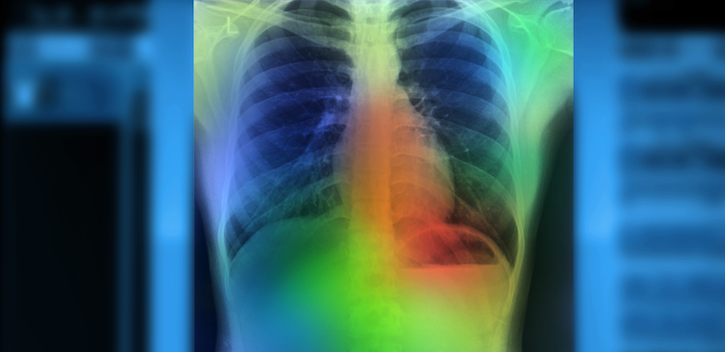

AI Accurately Detects Key Findings in Chest X-Rays in 10 Seconds

The tech can help physicians treat patients with pneumonia sooner.

Photo/Thumb ahve been modified. Courtesy of zapp2photo - stock.adobe.com.

An artificial intelligence (AI) system accurately identified key findings in chest X-rays of patients in the emergency department suspected of having pneumonia in just 10 seconds, researchers from Intermountain Healthcare and Stanford University reported at the European Respiratory Society’s International Congress 2019.

The research team used CheXpert, an automated chest X-ray interpretation model that uses AI, to review images taken at emergency departments at Intermountain hospitals in Utah. The Stanford Machine Learning Group used 188,000 chest imaging studies to create CheXpert, which determines what is and is not pneumonia on an X-ray.

CheXpert outperformed the current system and created the report in less than 10 seconds, compared to 20 minutes to hours with the natural language processing tool.